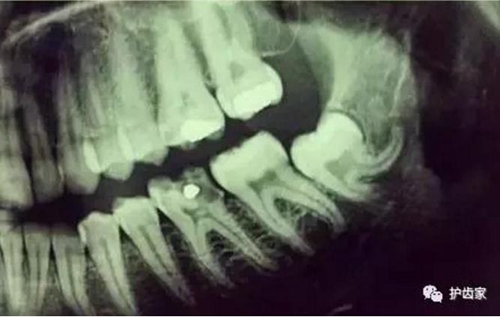

智齒周圍是牙槽骨,前面緊挨著第二磨牙,智齒下方大約兩三毫米遠(yuǎn)有一下頜神經(jīng)管,這神經(jīng)主要是下頜牙齒及下唇部位的知覺神經(jīng),一旦斷了,就會失去知覺。

根神經(jīng)線位置千變?nèi)f化,有些離智齒牙根很遠(yuǎn),有些很近,有些甚至穿過智齒根部。

拍片是為了了解智齒周圍情況,也是為了了解智齒結(jié)構(gòu),牙根結(jié)構(gòu)千變?nèi)f化,有可能是融合成一個根,也可能是八爪根。不同牙根不同位置及方向,只有通過拍片來確認(rèn)。

拍片也為了了解下頜神經(jīng)與智齒的關(guān)系,一般離得近,有醫(yī)療風(fēng)險的,基本沒有醫(yī)生愿意拔,現(xiàn)在沒人為了幾百元,賠上自己的職業(yè)生涯。誰都怕拔智齒,敲打智齒,一不小心,碰到神經(jīng),就攤上大事了。有理都說不清。

通過拍片可以了解牙齒本身:生長方向,牙根數(shù)目,牙根是否彎曲,膨大等。

與重要解剖結(jié)構(gòu)的位置關(guān)系:如上頜磨牙與上頜竇的關(guān)系;下頜磨牙與下頜神經(jīng)管的關(guān)系;兒童在混合牙列期恒牙與乳牙胚的關(guān)系等??梢詼p少拔牙的風(fēng)險。